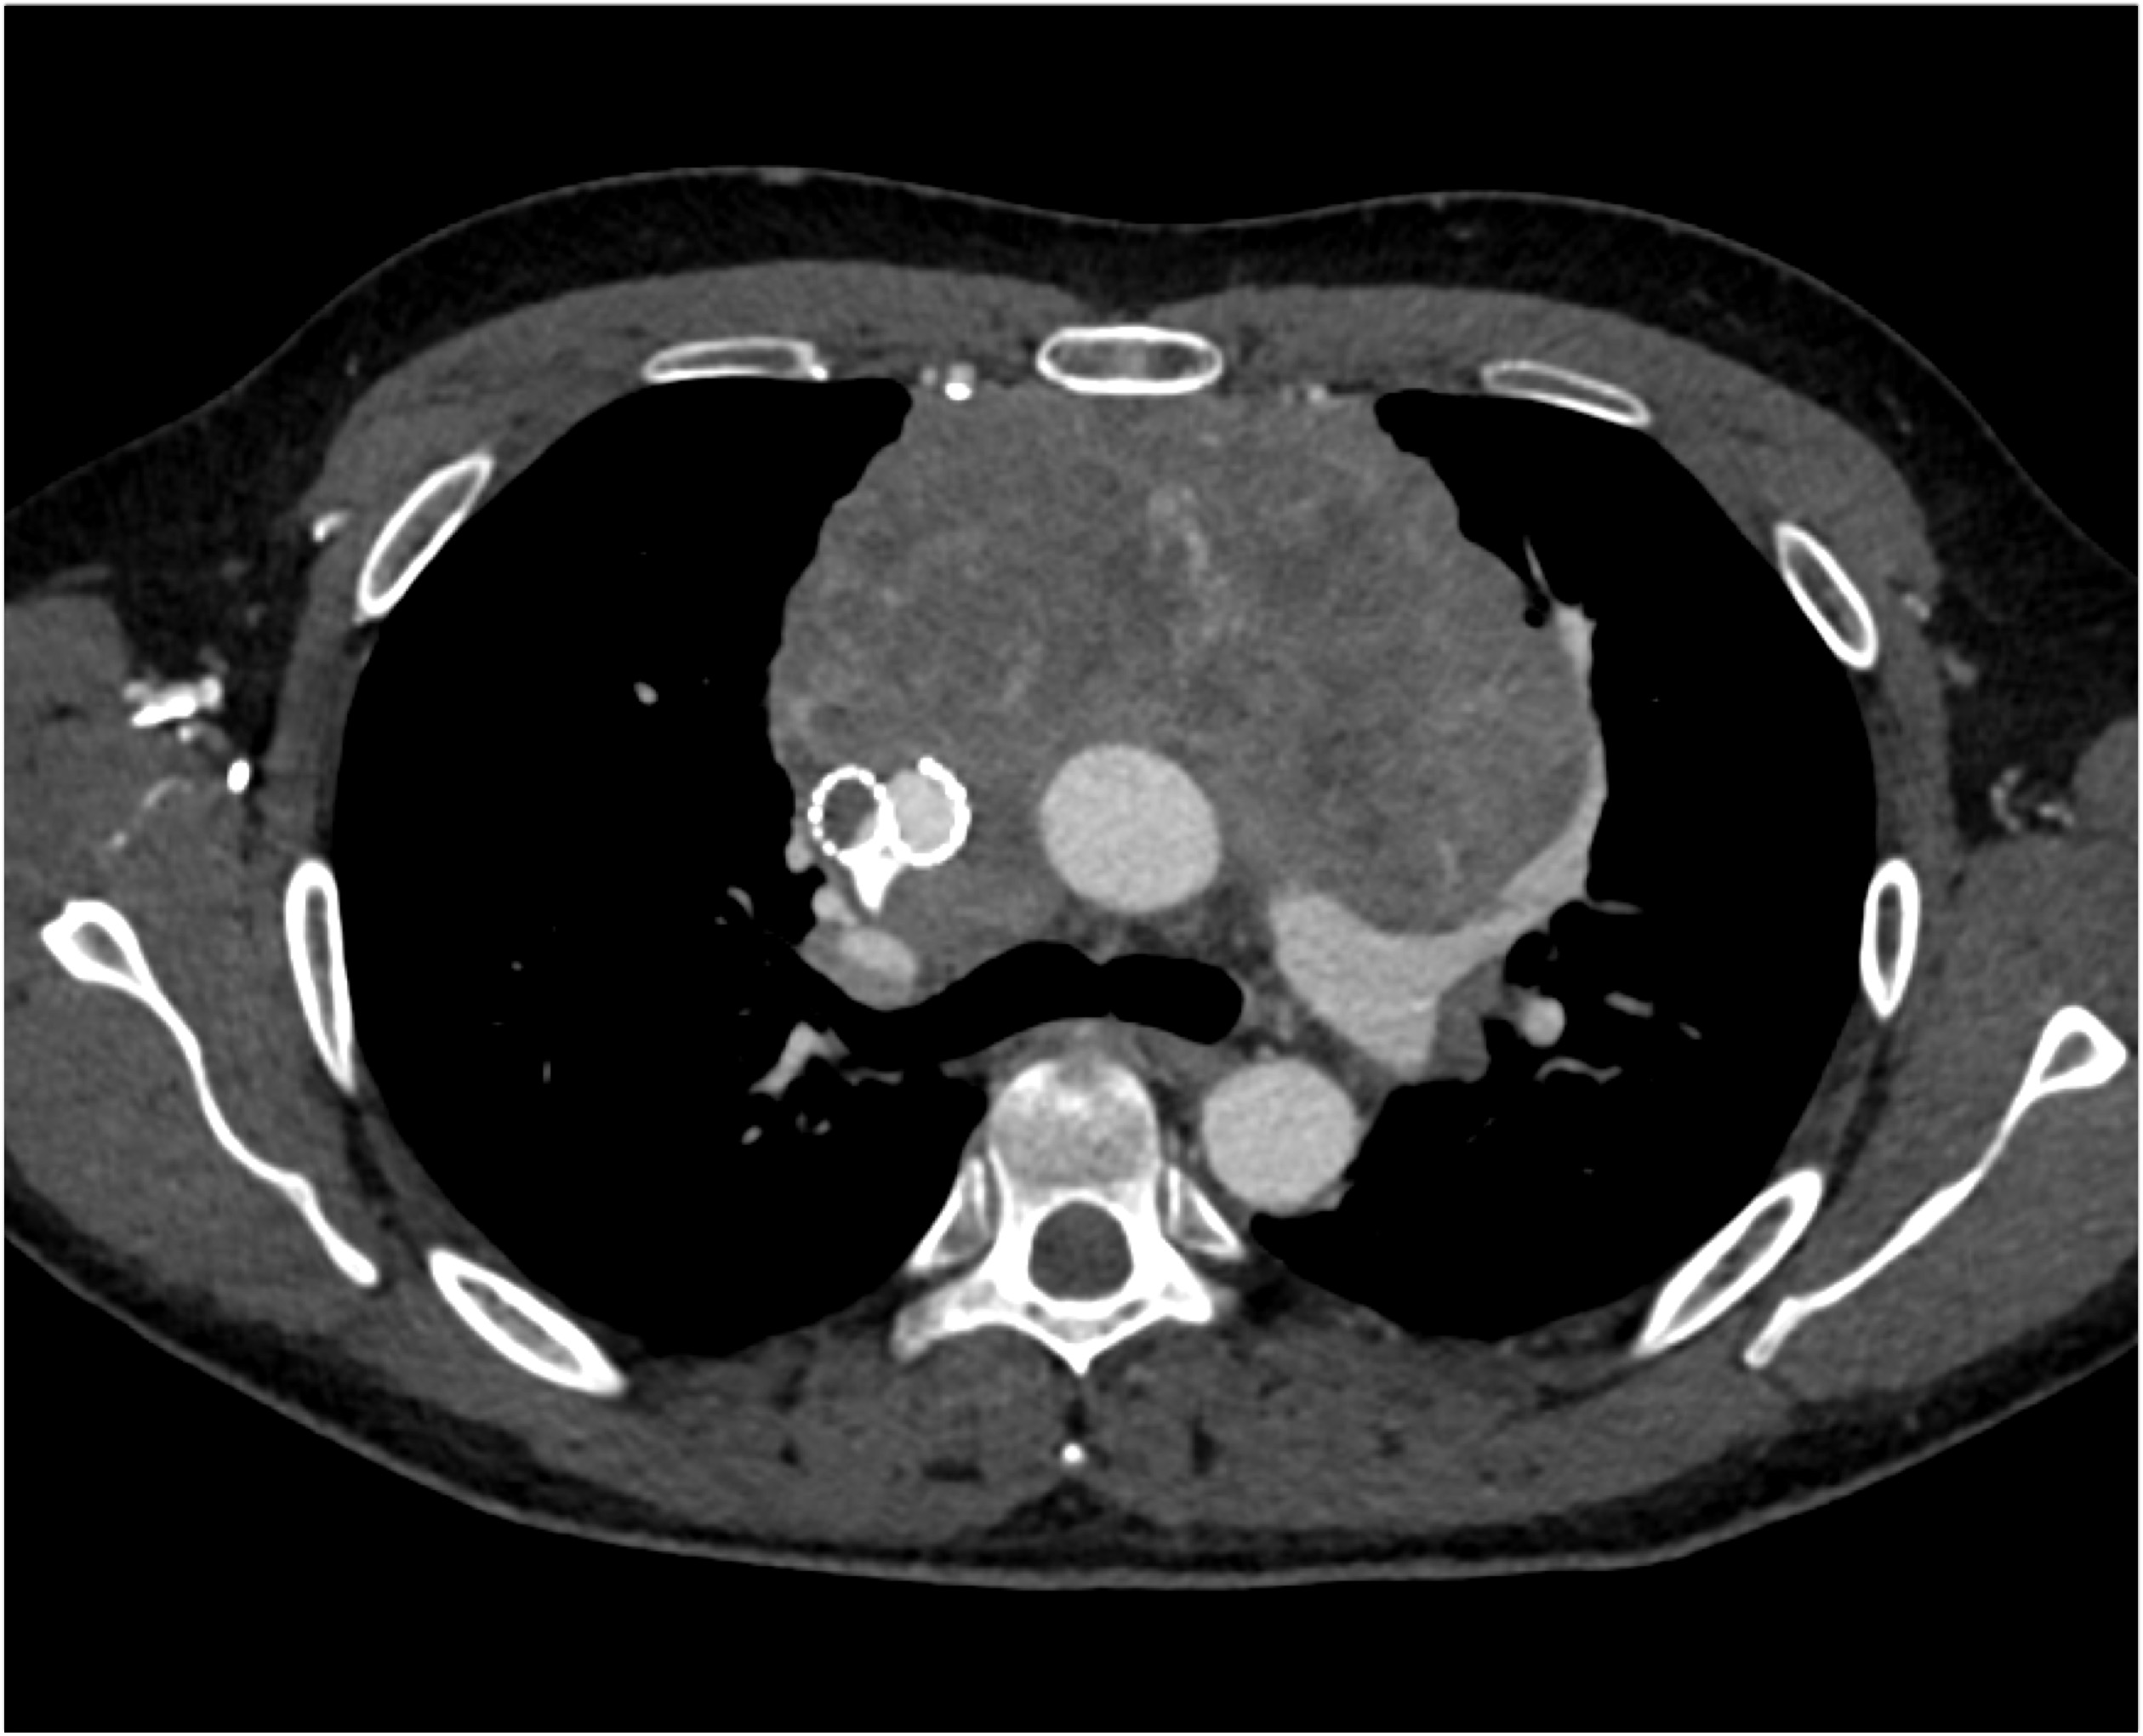

- Evaluate the CT images of each question carefully.

- Click on thumbnail images to view a larger version of the images.

- Take time to make the call on the diagnosis for each individual question.